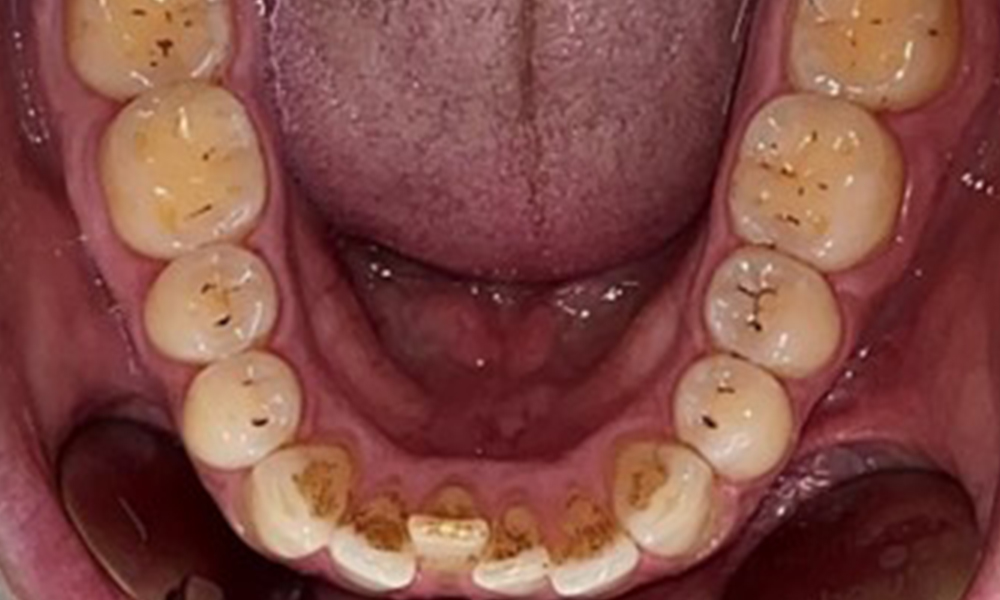

Occlusal view of the mandible.

Fig. 4: Occlusal view of the mandible, © Dr R. Krapf

There were no pathological extraoral findings. During intraoral examination, inspection of the frontal view revealed brownish discolouration near the keratinised gingiva and at the transition to the moveable mucosa (Fig. 2), which could be attributed to nicotine consumption. Whitish mucosal lesions were observed on the palate, particularly near the maxillary molar palatal surfaces, indicating increased keratinisation and can also be attributed to nicotine consumption. The tongue was covered with a removable white and brownish coating.

The patient has full dentition with a total of 28 teeth. There were noteworthy erosions and attritions. (Fig. 4, Fig. 5). Due to bruxism, the patient has been wearing a splint with an adjusted bite block at night for many years. The erosions were caused by long-term consumption of isotonic beverages. No periodontal bone loss or active caries were observed.

Full complement of adult teeth with no caries or radiologically recognizable bone loss was observed (Fig. 6). Radiological enamel and cusp loss were particularly evident on 36 and 37.